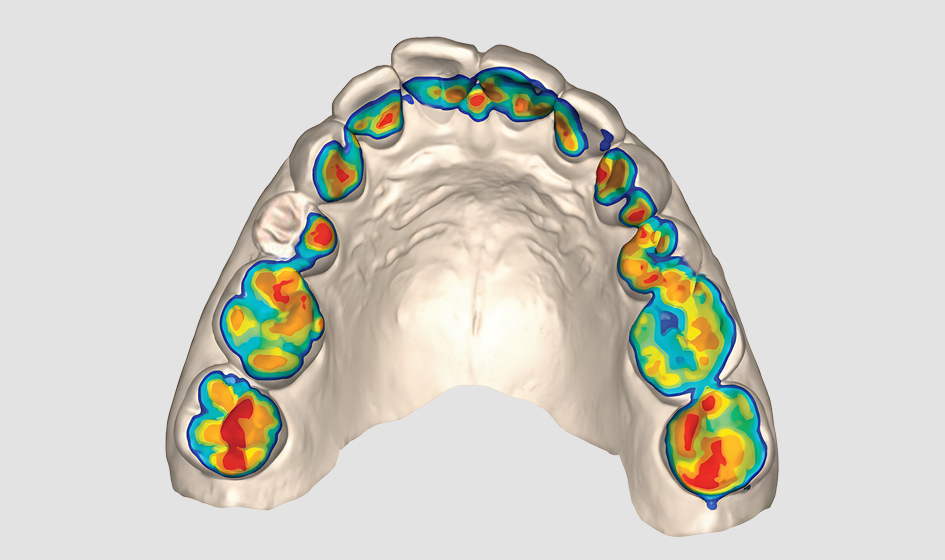

Our team’s expertise in bite analysis allows us to identify how your tooth alignment and jaw position contribute to TMJ symptoms and overall oral health. Using advanced technology and careful evaluation, we can determine whether orthodontic treatment, bite adjustment, or other therapies would be most effective for relieving your symptoms. Our comprehensive approach considers how TMJ treatment integrates with your overall oral health plan, ensuring solutions that support both comfort and long-term dental health.

Our team’s thorough evaluation identifies all factors contributing to your TMJ symptoms, including bite alignment, muscle tension, and joint function. This comprehensive understanding allows for more effective, targeted treatment approaches.

Our team uses a combination of clinical examination, digital imaging, and bite analysis to evaluate your TMJ function. We assess jaw movement, listen for joint sounds, examine your bite alignment, and use advanced technology to understand how your teeth and jaw work together. This comprehensive approach identifies all contributing factors.